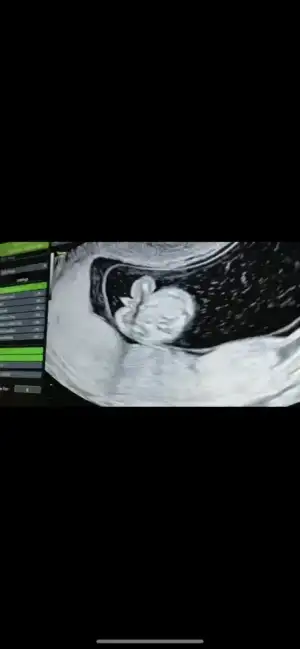

- Janna - - Janna - canım sen bana kız dedin çoğu kişi kız dedi 😅 doktor da ilk salı günü kıza benziyor gibi demişti ama bana bugün pipi resmi verdi, Allah aşkına sende bak 🤣 kafam karıştı cidden

Bu saatten sonra pek dönmez gibi dedi sonra da baktı bi iyice erkek bu erkek dedi.

Muayene zamanın geçmeden bi daha gelirsin bi daha bakarız dedi

Ekliyorum buraya fotoyu daha doğrusu anlayan herkes benim kafam karıştı..

yok artık benim bile kafam karıştı şaşırdım erkekmi şimdi kesin hani yuvarlak kese kızdı btün teoriler yalan oldu bende benimki herhalde erkek diyodum dahada meraklandım şimdi😂

Kızlar Dilos6342 Dilos6342 cinsiyet tahmini ile ilgili değişikliği yazınca bende bi tereddütte kaldım. Bize de 12+5. de resimlerdeki yerlere zoom yaparak erkek demişti. - Janna - - Janna - ne diyorsun bu erkek görüntüsü mü 😅